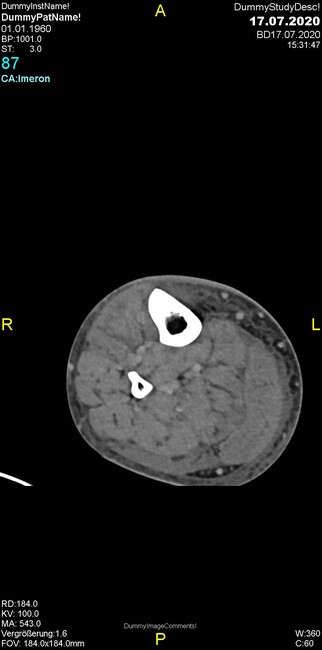

Um welche Modalitäten handelt es sich?

- Röntgen p.a. und lateral, CT coronar Knochenfenster, CT axial Weichgewebsfenster

Was fällt in der Projektionsradiographie auf?

- Aufhellungslinie in Projektion auf die Femurkondylen

Was fällt in der CT im Knochenfenster auf?

- Osteolyse der Tibiametaphyse unter Beteiligung der Kortikalis